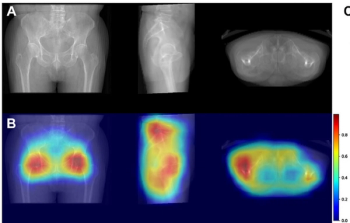

Employing reconstructed radiographs from 3D hip CT scans, a deep learning model demonstrated a higher concordance index (C index) and higher two- and three-year AUCs than multiple imaging models and three clinical models for predicting subsequent fracture risk in patients with hip fractures.